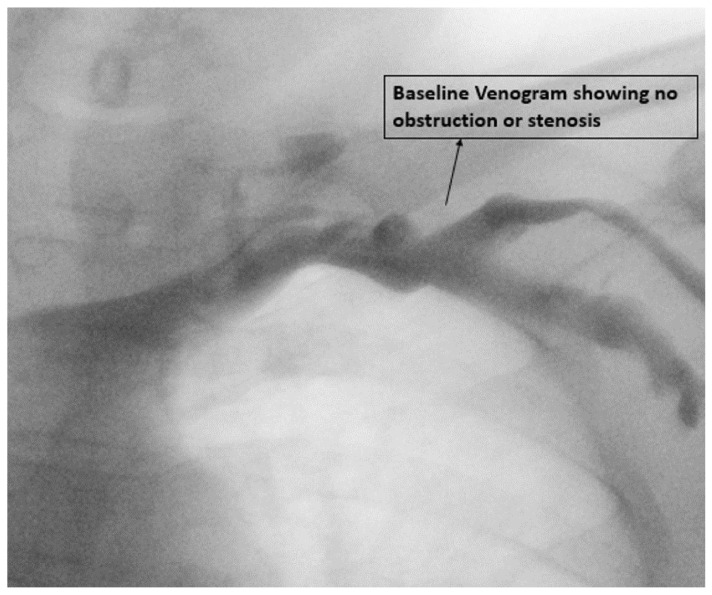

Methods: This study was a single-center prospective, observational study. Demographic, clinical, procedural, and device data was collected. All patients underwent a preimplant contrast and repeated venography at twelve months to look for upper limb venous anatomy, obstruction, or collaterals.

Abstract Image